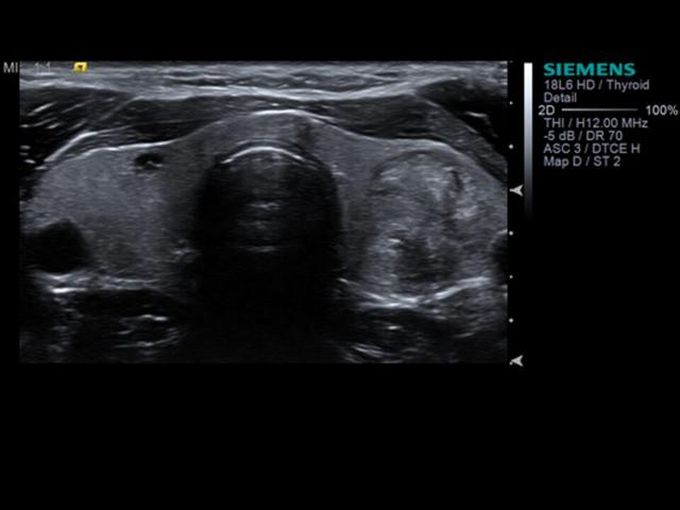

Кроме новой техники, можно заказать восстановленные медицинские системы: ультразвуковые сканеры, томографы, флюороскопы, ангиографы и хирургические установки С-дуга.